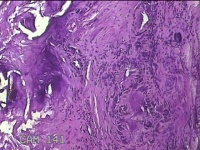

左外踝包块

性别

男

年龄

31岁

临床诊断

皮下结节

一般病史

发现左外踝包块1年余。

标本名称

大体所见

灰白暗红色包块1.8x1.3x0.7cm一个,表面糜烂,切开包块,内见大量石灰样物,内壁粗糙。

去了解病史,应该是痛风结节。